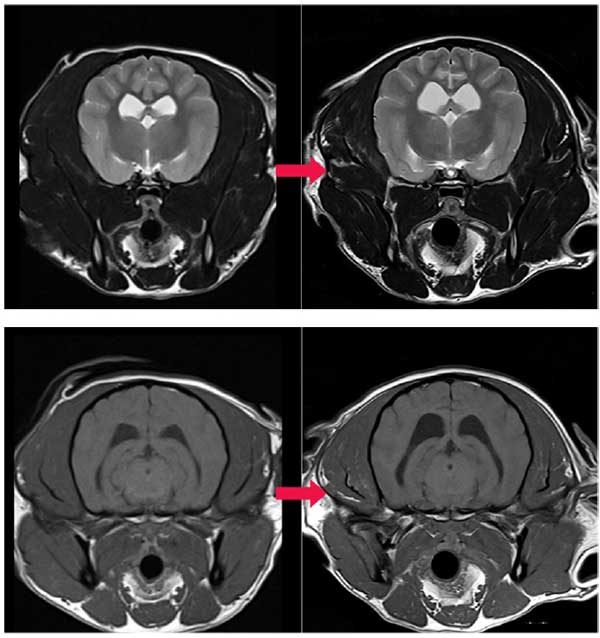

2023년 말 최첨단 AI MRI 소프트웨어를 도입한 이안은 촬영시간 단축과 영상 품질 극대화라는 두 마리 토끼를 동시에 잡았다. AI 소프트웨어의 딥러닝 알고리즘을 통한 이미지 재구성과 노이즈 제거, 선명도 향상은 보다 신속하고 정확한 진단을 가능하게 했으며, 보호자와 반려동물 모두에게 높은 만족도를 제공하고 있다.

이미지 퀄리티 또한 높아졌는데, 정밀한 판독이 가능해져 질병의 조기 발견과 정확한 진단을 통한 치료전략 수립에 큰 진전을 이뤄냈으며, 이안 전담 마취팀의 철저한 관리까지 더해져 반려동물 검사 전 과정에서 신뢰도 높은 의료 서비스를 제공하고 있다는 평가를 받고 있다.